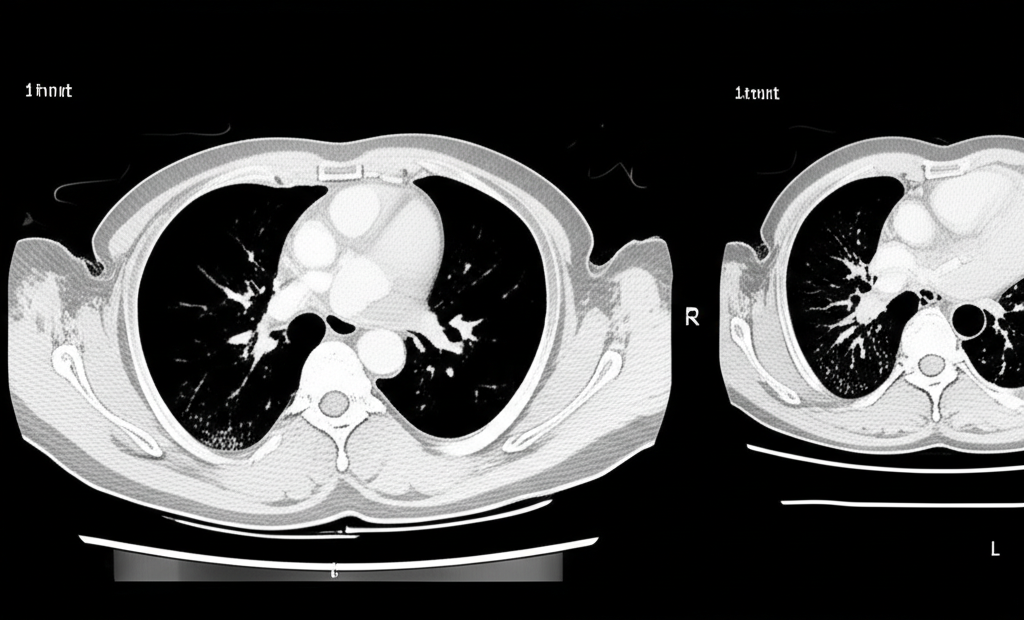

폐 CT는 폐 질환 진단에 매우 중요한 역할을 하는 영상 검사입니다. 흉부 X선 검사보다 훨씬 더 자세한 정보를 제공하여 폐암, 폐렴, 만성 폐쇄성 폐질환(COPD) 등 다양한 질환을 조기에 발견하고 정확하게 진단하는 데 도움을 줍니다. 건강 검진 시 폐 CT 검사를 고려하는 것은 건강한 삶을 유지하는 데 매우 현명한 선택입니다.

폐 CT로 알 수 있는 것은 폐암뿐만 아니라 폐렴, 결핵, 기관지확장증, 간질성 폐질환 등 다양한 폐 질환을 진단하는 데 유용합니다. 이러한 질환들은 호흡 곤란, 기침, 가래 등의 증상을 유발할 수 있으며, 심한 경우 생명을 위협할 수도 있습니다. 폐 CT 검사를 통해 이러한 질환들을 조기에 발견하고 적절한 치료를 받으면 질병의 진행을 늦추고 합병증을 예방할 수 있습니다.

폐 CT는 폐렴의 종류와 범위를 파악하고, 합병증 발생 여부를 확인하는 데 유용합니다. 특히 면역력이 약한 환자나 노인의 경우, 폐렴이 심각한 합병증으로 이어질 수 있으므로 폐 CT 검사를 통해 정확한 진단과 치료 계획을 수립하는 것이 중요합니다.

폐 CT는 COPD 환자의 폐기종 정도, 기관지 확장 여부, 폐렴 발생 여부 등을 평가하는 데 사용됩니다. 이를 통해 COPD의 진행 정도를 파악하고, 적절한 치료 계획을 수립하여 환자의 삶의 질을 향상시킬 수 있습니다.